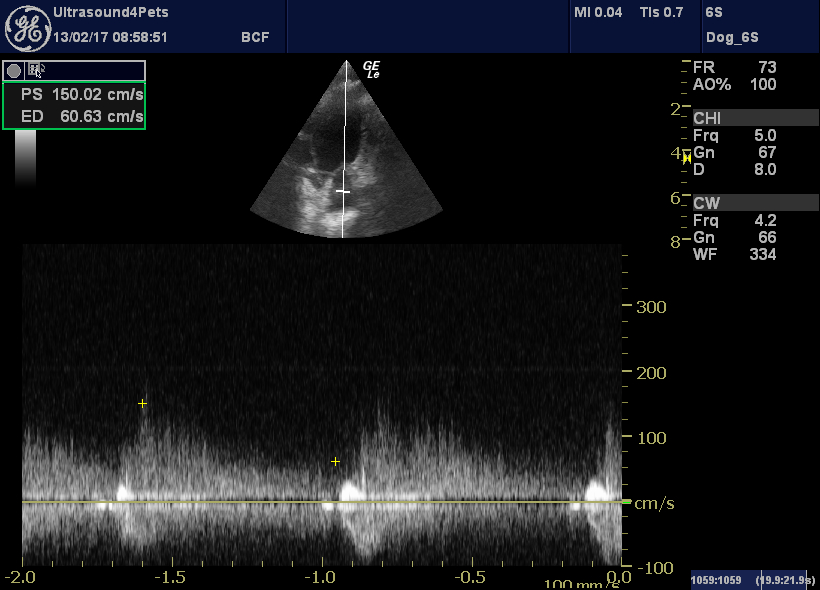

From www.vetpracticesupport.com

Canine patent ductus arteriosus (PDA) echocardiography Vet Practice Pda Meaning Veterinary — patent ductus arteriosus (pda) is one of the most common congenital heart defects in dogs, accounting for approximately 10 to 30. learn about patent ductus arteriosus (pda), a congenital heart defect in dogs and cats that causes blood to shunt from the aorta to the lungs. — a patent ductus arteriosus (pda) is an arterial shunt. Pda Meaning Veterinary.

Canine patent ductus arteriosus (PDA) echocardiography Vet Practice Pda Meaning Veterinary The ductus arteriosus is a. learn about patent ductus arteriosus (pda), a birth defect that causes abnormal blood flow in the heart and lungs. — a patent ductus arteriosus (pda) is an arterial shunt between the pulmonary artery and the aorta that is. patent ductus arteriosus (pda) is one of the most common congenital heart defects in. Pda Meaning Veterinary.